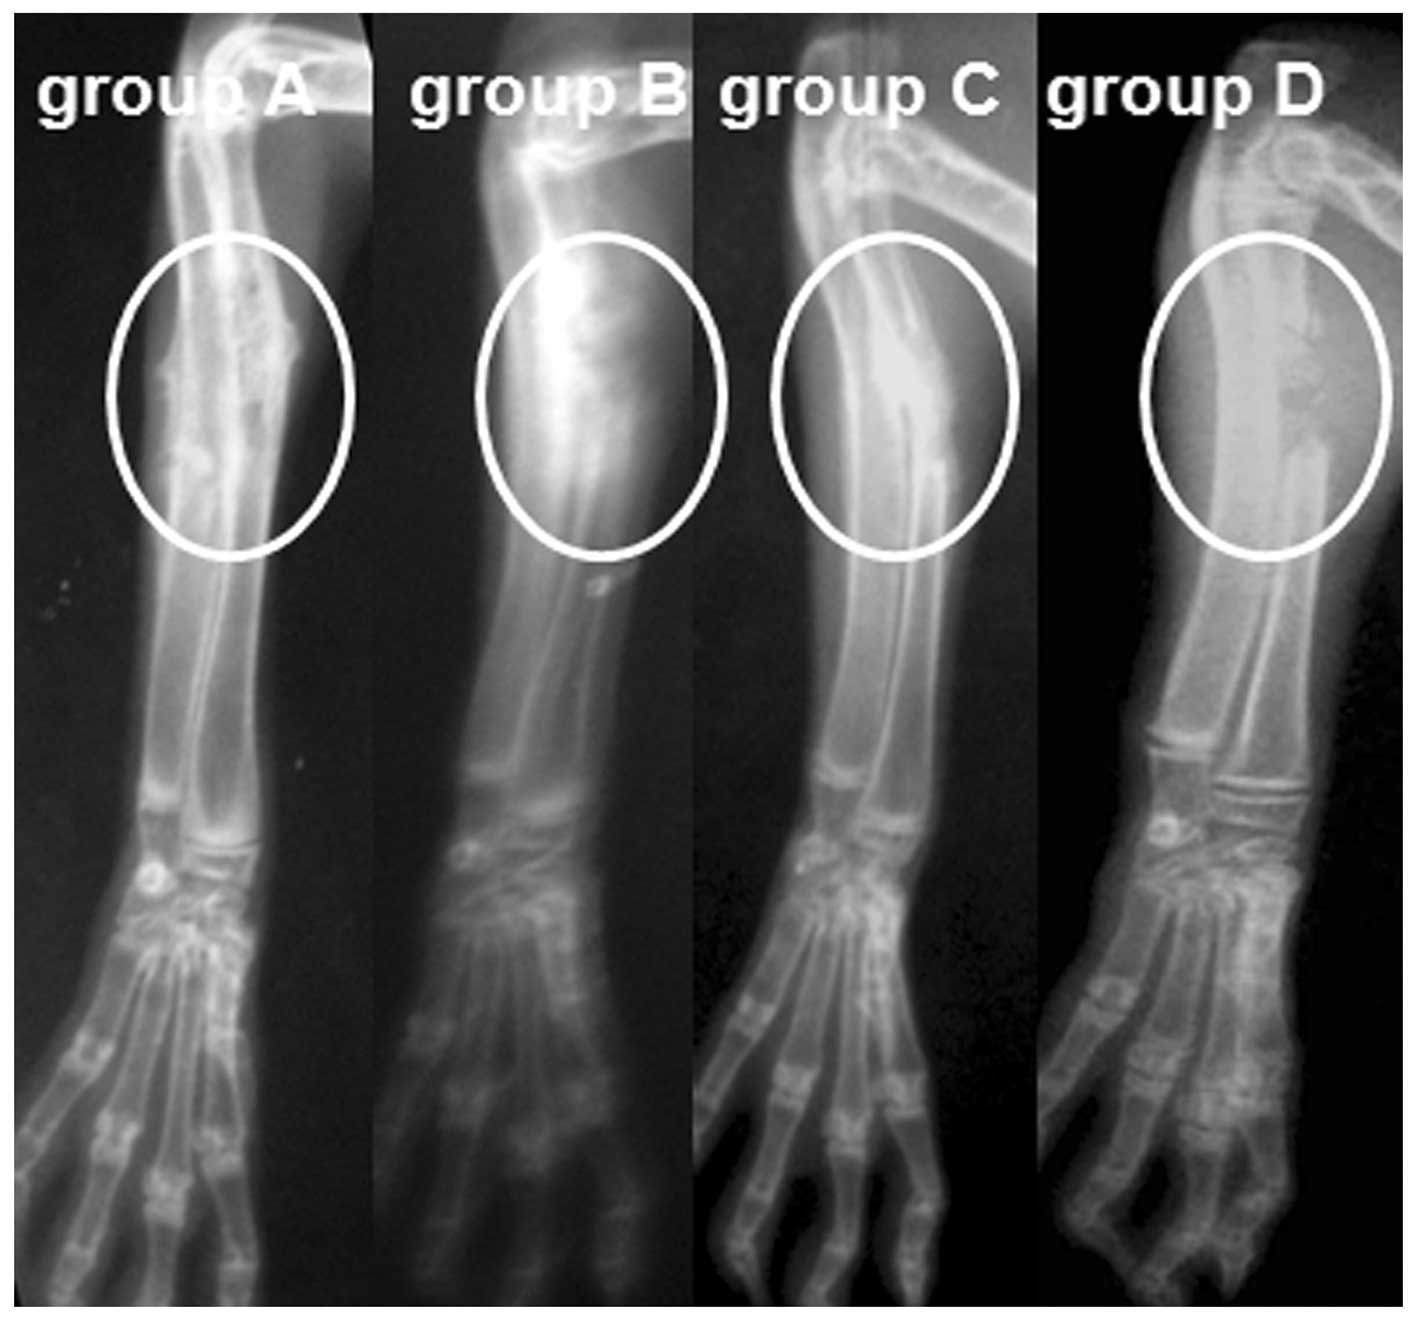

Through radiological observation, a standard defect shadow was observed at the radius of rabbits in group D, while in groups A, B and C, the defects were filled with high-density material, as revealed by the postoperative radiograph. In animals of group A, a bone callus formed by the 4th week, defects started repairing by the 8th week and the medullary cavity was recanalized by the 12th week. By comparison, the defects appeared to be delayed union or nonunion in group C (delayed union, 7; nonunion, 5) and group D (nonunion, 11), and osteomyelitis was observed in group B (10/10) at week 12 (Fig. 4).

Figure 4

At the 12th week, bone defects were repaired and the medullary cavity was recanalized in group A. In comparison, osteomyelitis formed in group B, nonunion of bone occurred in group C and no bone formed in the defect of group D (circle, defect area).